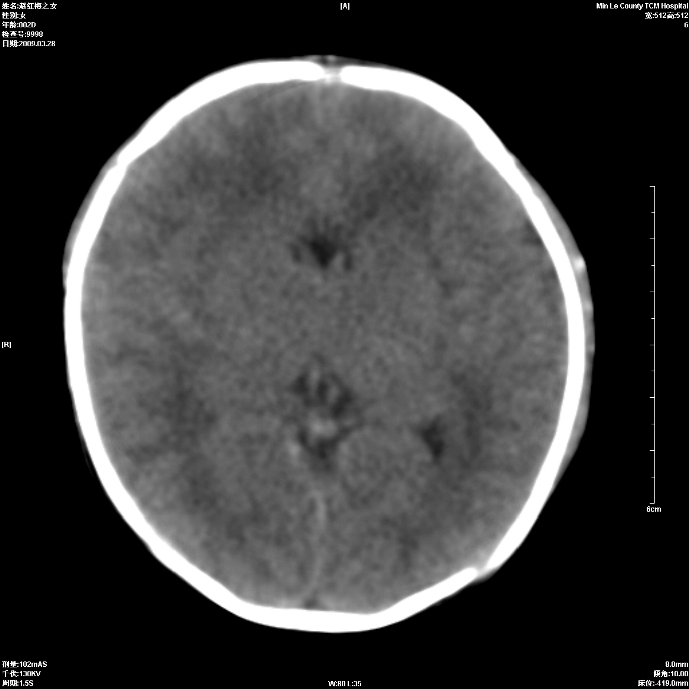

标题: PED1815:患儿出生两天,哭闹不安,囟门饱满 [打印本页]

标题: PED1815:患儿出生两天,哭闹不安,囟门饱满

支持考虑新生儿缺血缺氧性脑病伴蛛网膜下腔出血,请结合临床,建议随访复查

支持缺血缺氧性脑病伴少量蛛网膜下腔出血。

若有窒息史,考虑缺血缺氧性脑病伴少量蛛网膜下腔出血。

考虑新生儿缺血缺氧性脑病伴蛛网膜下腔出血

建议mri排除缺血缺氧性脑病!